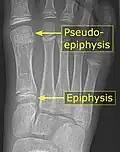

Es común en los niños tener una pseudoepífisis del primer metatarsiano.